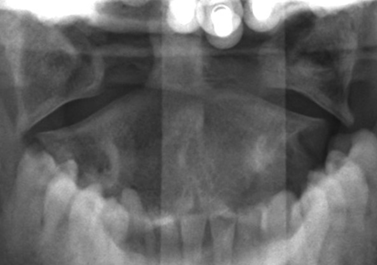

3. Pseudo-Jefferson’s fracture

Psuedo-Jefferson’s fracture or pseudospread of the atlas on the axis refers to the normal overhang of the lateral masses of C1 over the lateral edges of the body of C2. This is a normal physiologic finding in children up to the age of 7, most likely due to differential speed of growth of the atlas versus the axis.4 6-mm of overhang is the accepted maximal value of normal overhanging when adding the offset of the sides bilaterally.

Figure 4: Normal lateral overhang of the C1 masses relative to the C2 lateral masses. Case courtesy of Radiopaedia.